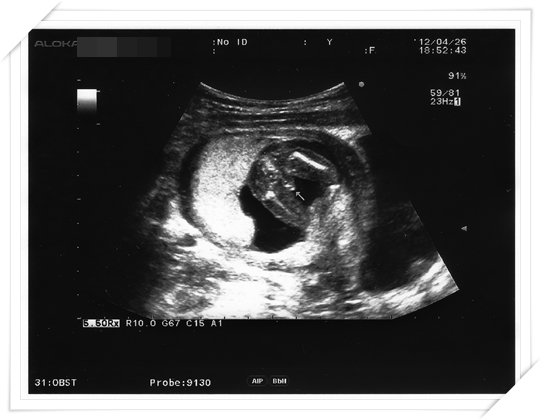

總算 等到15週又到了例行產檢的時候

我們總算開口問了醫生啦

然後醫生也很爽快

超音波一往肚子照 馬上就找到一個很清楚的姿勢照給我們看啦

當下我看到還真的是覺得 怎麼這麼好笑呢!!!

就是下面這張照片啦

恩~~~~~ 因為我週數已經夠大啦

所以照出來的 不是甚麼三個小白點或是甚麼兩個小黑點

就是直接整個有點小害羞的部位啦~~~~~~~

大家看到了嗎??

照片裡面箭頭指的 就是小男生的…. “重要部位”啦! 哈哈哈

所以 答案揭曉! 我懷的是一個很GENKI的小男生囉!!